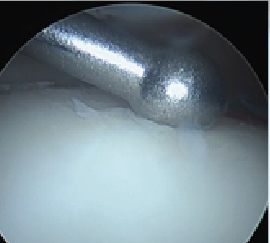

A more recent addition on the market is a cryopreserved viable osteochondral allograft called Cartiform (Osiris Therapeutics/Arthrex). This too is harvested from a juvenile host. It is comprised of extracellular matrix, viable chondrocytes and chondrogenic growth factors. It is a scaffold onto itself and promotes an appropriate structure for phenotypic expression of new cartilage cells. Cartiform provides the benefit of a fresh allograft without the challenges of its use from the standpoint of procurement and infection transmission. One can see the application of such a graft to a lesion on the central medial aspect of the talus (see above left photo).